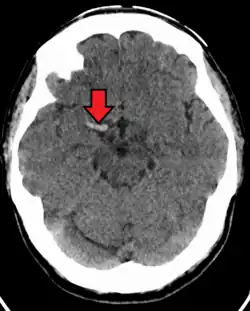

Acute thrombus in the right MCA M1 branch

A stroke is the rapid decline of brain function due to a disturbance in the supply of blood to the brain.[6] This can be due to ischemia, thrombus, embolus (a lodged particle) or hemorrhage (a bleed).[6]

In thrombotic stroke, a thrombus (blood clot) usually forms around atherosclerotic plaques. Since blockage of the artery is gradual, the onset of symptomatic thrombotic strokes is slower. Thrombotic stroke can be divided into two categories — large vessel disease or small vessel disease. The former affects vessels such as the internal carotids, vertebral and the circle of Willis. The latter can affect smaller vessels, such as the branches of the circle of Willis.